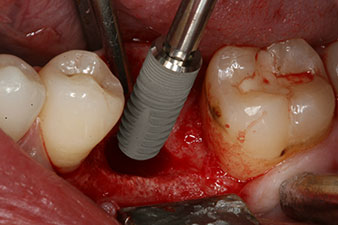

SmartPeg

Fig. 4: SmartPeg measuring posts screwed on to measure the implant stability quotients with the integrated W&H Osstell ISQ module.

The torque used for the machine-driven placement was 43 Ncm. In addition, after screwing a measuring post (SmartPeg) specially matched to the implant, the ISQ value was measured with the probe of the W&H Osstell ISQ module.

This module is an optional extra for the W&H Implantmed and is docked to the implantology motor (see Fig. 11). The dimensionless ISQ value immediately after insertion was 64 orovestibular and 68 mesiodistal (maximum value = 100).

These values could have indicated open healing or even immediate restoration. Due to the insufficient crestal bone volume at the implant, the region was augmented with the bone chips collected during preparation of the implant bed and sutured to exclude saliva.